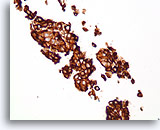

Papilloom, Borst FNA, Celblok.

Immunokleuring met p63 van de coupes van de patiënt in afbeelding 23-25 helpt de myoepitheliale cellen te markeren die door deze papilloom verstrooid zijn.

10X

Papilloom, Borst FNA, Celblok.

Immunokleuring met p63 van de coupes van de patiënt in afbeelding 23-25 helpt de myoepitheliale cellen te markeren die door deze papilloom verstrooid zijn.

10X